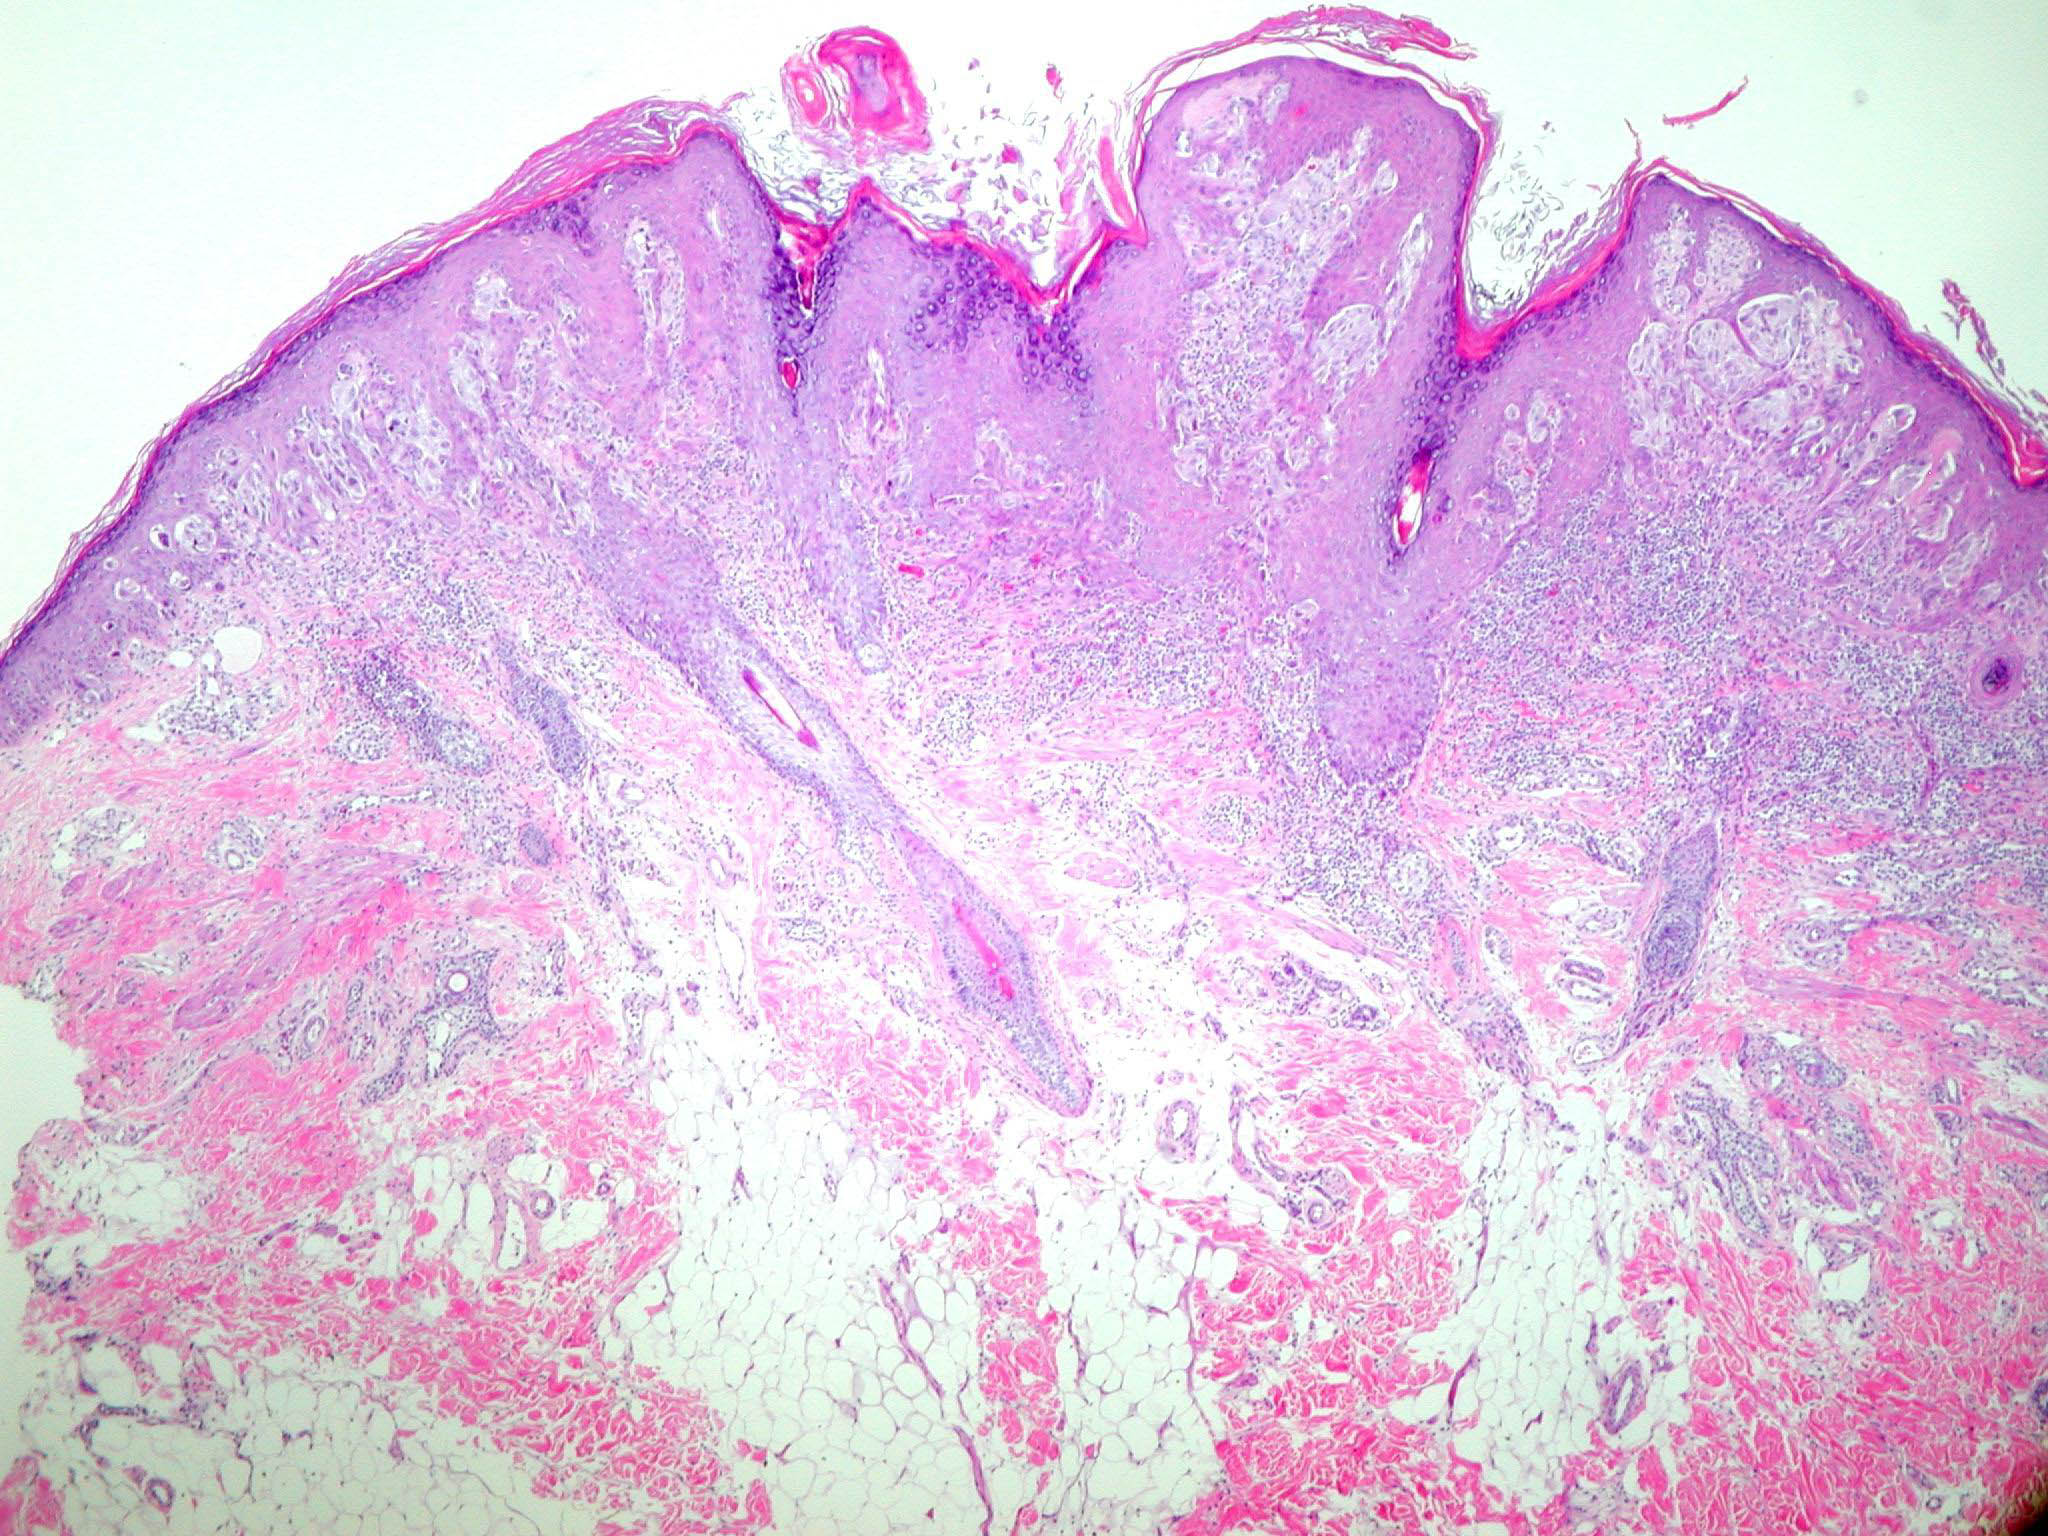

Spitz naevus (juvenile melanoma) = وحمة سبيتز _الميلانوم الفتوي